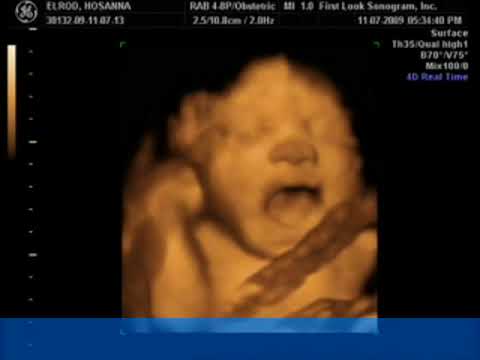

ECOGRAFIA 4D

Vídeo con una ecografia en 4D donde se puede apreciar todo el proceso y las diferencias entre un tipo y otro de ecografia.